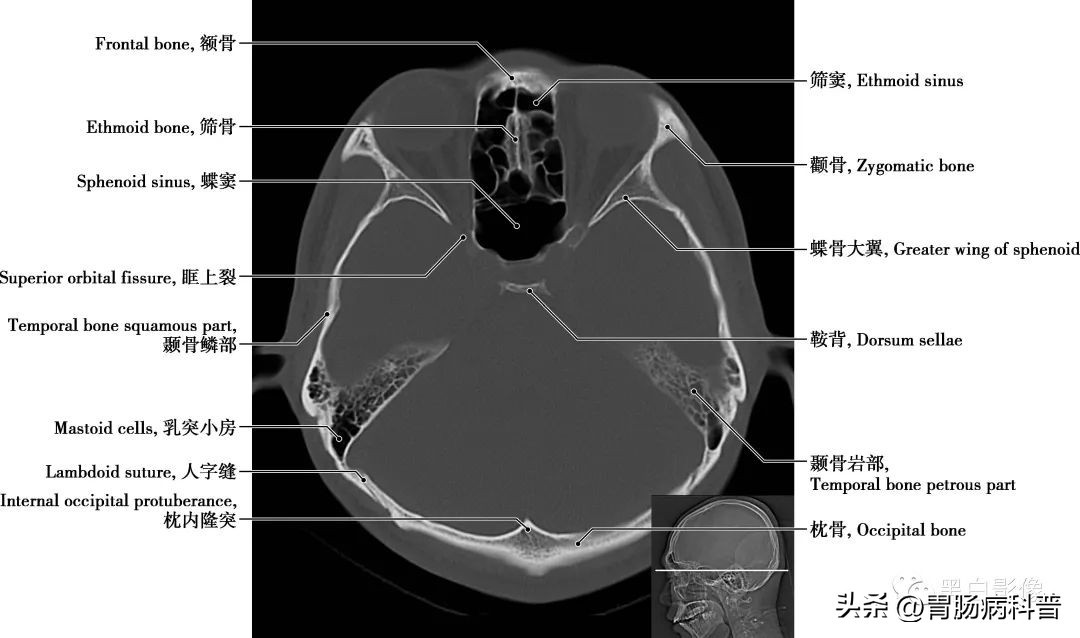

图1-2-14 经第四脑室中央轴位切面

颞骨岩部 岩部前上面位于颅中窝,中部有一弓状隆起,外侧为鼓室盖,靠近锥体尖处,有稍凹的三叉神经压迹;其后上面位于颅后窝,近中央处有内耳门。后上面和前上面相接处为岩部上缘。岩部下面近中央部有颈动脉管外口,颈动脉管在岩部内侧半通过,在锥体尖处形成颈动脉管内口;外口的后方为颈静脉窝,它与后方枕骨上的颈静脉切迹围成颈静脉孔